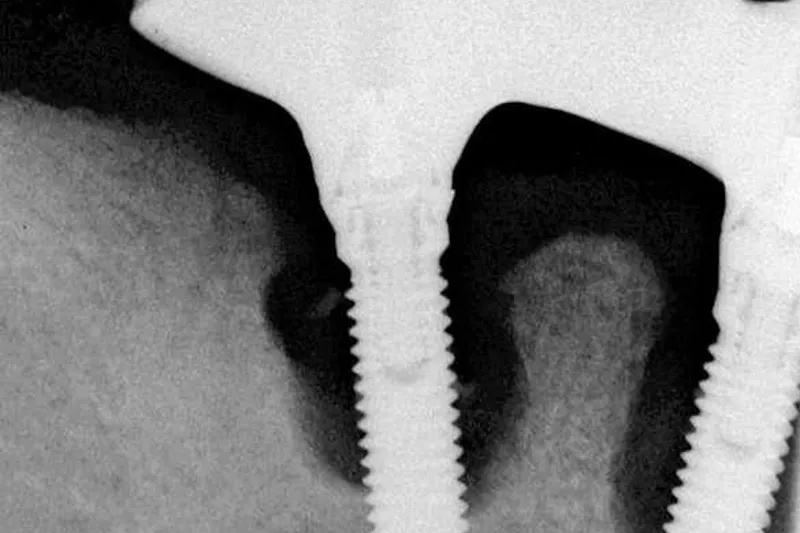

Metaanalyser indikerer en dobbelt så stor risiko for tab af implantater hos rygere sammenlignet med ikkerygere, og mister man et implantat, medfører det ofte parodontale forandringer, der er vanskelige at genskabe. Periimplantitis er en plakassocieret inflammationssygdom, som rammer 10-20 % af patienter med et eller flere dentale implantater. Undersøgelser viser, at risikoen for at udvikle periimplantitis er 3,6-4,6 gange større for rygere sammenlignet med ikkerygere.

- Sene komplikationer (periimplantitis med tab af implantatbærende kæbeknogle og omkringliggende blødtvæv)